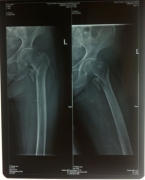

7月9日,莆田盛興醫(yī)院為一名89歲的女性髖部骨折患者順利實施了手術。   數(shù)日前,東……

近日,平海鎮(zhèn)90歲高齡的周阿婆即將出院。她感慨地對筆者說:“真沒想到我還能下床走路……